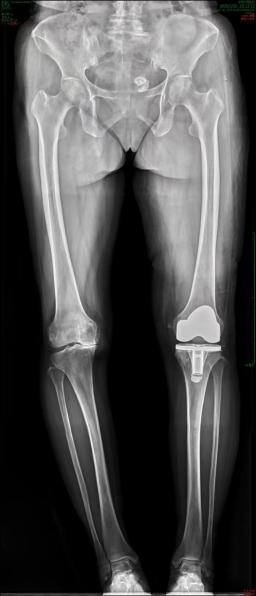

此次接受手术的,是一名62岁男性患者,长期受到膝关节严重病变的折磨,膝关节疼痛难忍,行走困难,日常生活受到极大影响。传统的全膝关节置换手术虽然能够有效治疗该疾病,但由于手术操作的复杂性和患者个体差异,手术效果存在一定的不确定性。谭红略主任团队经过详细评估和充分讨论,决定引入机器人辅助系统,为患者制定个性化的精准手术方案。

手术机器人辅助系统的应用,极大地提升了手术的精准性和安全性。该系统在术前通过对患者的CT影像进行精准分析,能够构建出膝关节的三维立体模型,为医生提供直观、清晰的解剖结构信息。基于这些数据,谭红略主任团队能够精确规划手术方案,确定假体的最佳尺寸、位置和角度,真正实现“量体裁衣”式的个性化治疗。

术中,机器人的机械臂犹如医生的“第三只手”,能够根据预设的手术方案,以毫米级的精度进行截骨操作,有效减少了手术误差和对周围组织的损伤。同时,机器人系统还具备实时监测和反馈功能,能够帮助医生及时调整手术参数,确保手术的每一个步骤都精准无误,极大地提高了手术的成功率和假体的使用寿命。

在谭红略主任的带领下,手术团队凭借丰富的经验和精湛的技术,与手术机器人紧密配合,顺利完成了此次全膝关节置换手术。术后,患者生命体征平稳,膝关节疼痛明显缓解,恢复情况良好。